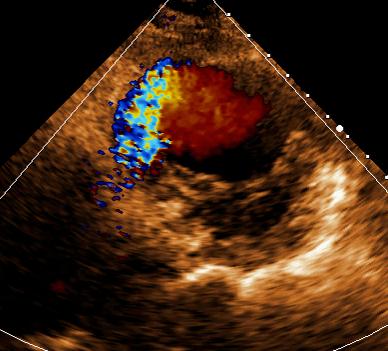

图 4 彩色多普勒超声示左位上腔静脉呈蓝色血流信号图 3 胸骨上窝切面